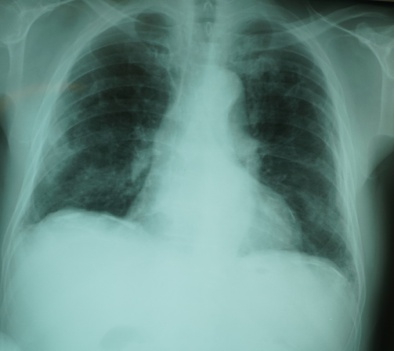

2. 職業ばく露 建設業

1995年から2017年まで建設国保組合と連携して1万~4万人の胸部レントゲン写真を読影してきた。2000年段階での読影結果を示した【図3】【図4】。

建築の労災事案の経過についての研究は、1998年から2012年11月までの14年間を、石綿肺管理2以上続発性気管支炎の合併症で療養した25名で観察した7)。結果は、

(1)観察期間の中央値は10(最短4~最長14)年で、14年間に死亡した者15名、現在当院通院中が10名であった。死亡した15名の死亡診断書の死因は、原発性肺がん6名、慢性呼吸不全6名(在宅酸素療法から呼吸不全死亡)、続発性気管支炎+肺炎が2名、間質性肺炎(UIP疑い)1名であった。胸部CT写真の読影では24名に、胸膜プラーク(医師3名一致20名、2名一致4名)が認められた(35.8%)。胸部CTの点状陰影(DOT’S陰影)密度増加は、4名(医師3名一致は1名のみで、医師2名一致が2名、医師1名指摘が1名)と判断が分かれた。【写真4】

2016年に実施した、建設業の60歳のHRCTによる石綿関連疾患の検討では、63名中27名に(胸膜プラーク25名、石綿肺0/1と胸膜プラーク重複例2名)に認め検出率40.3%であった8)。HRCTによる肺疾患の異常としては、63名中陳旧性瘢痕60名、肺気腫11名、肺のう胞12名,胸膜ゆ着7名、等であった。肺癌疑い2名、中皮腫疑い1名は現在経過観察中である。